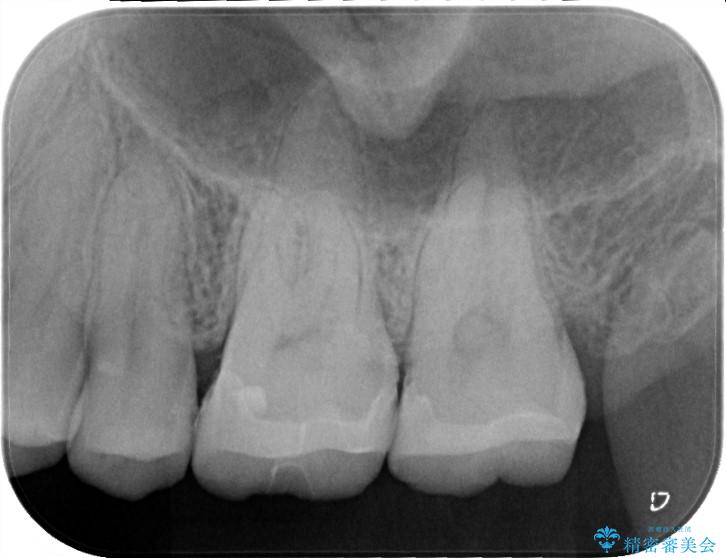

今ある金属の詰め物をメタルフリーのものにやりかえたいとの主訴で来院されました。

金属の詰め物を除去して虫歯の処置をした後にセラミックインレーにて修復しました。